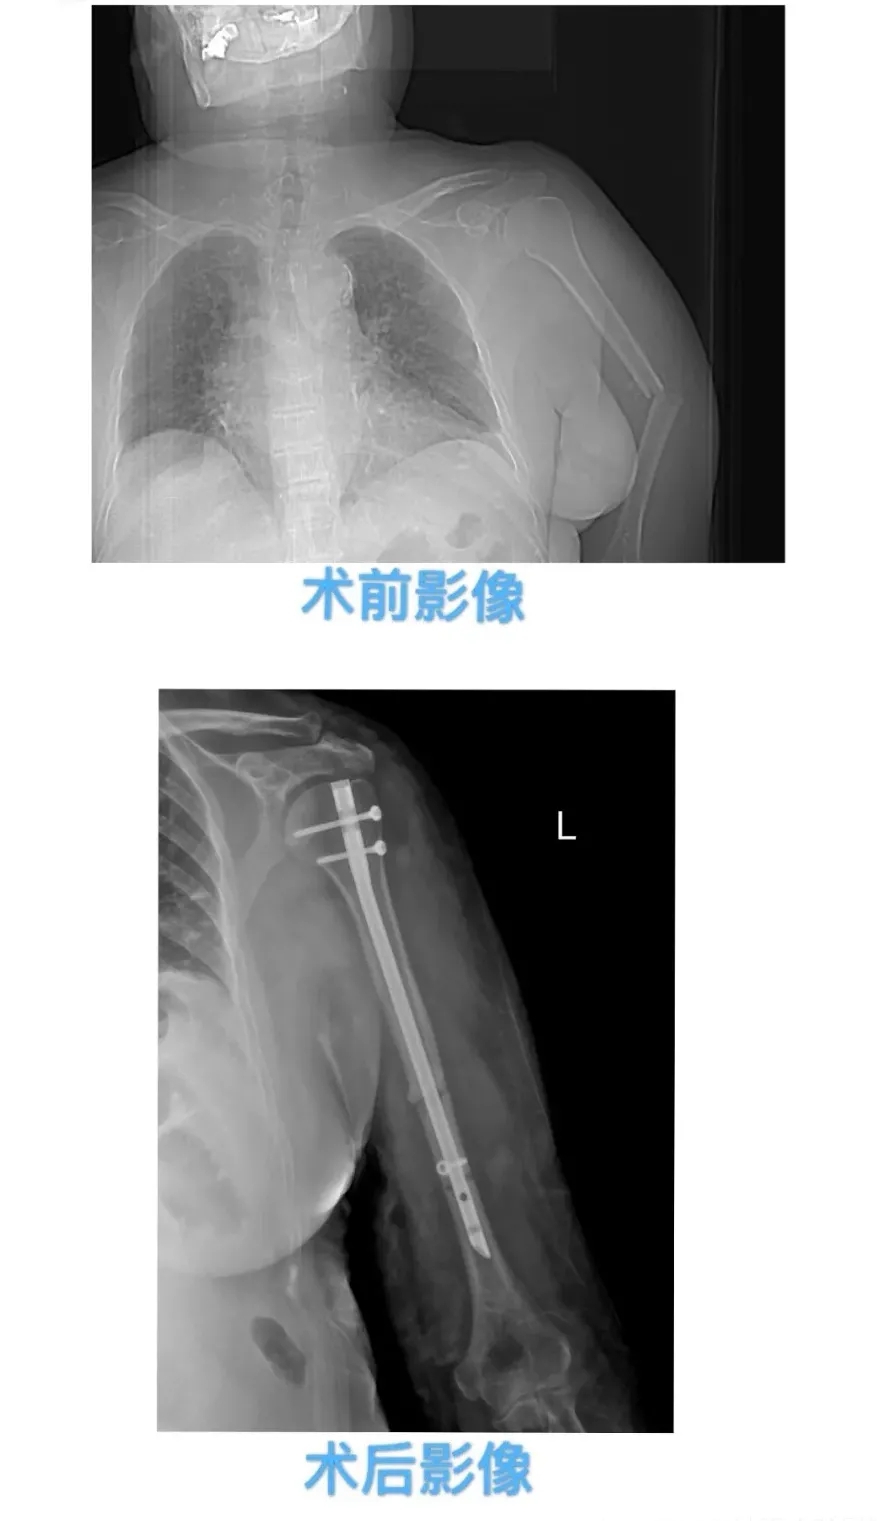

骨卫士特聘专家、莒南县红十字永康医院骨科主任王伟结合相关影像检查诊断其为“左侧髋臼粉碎性骨折”,建议采取手术治疗。王伟主任组织医院骨科专家组进行了全面的术前讨论,制定了详细的手术方案、术中应急预案及术后护理方案。在手术室及麻醉科等多学科的密切配合下,王伟主任凭借娴熟的手术技巧和丰富的临床经验,为患者实施“骨盆骨折切开复位内固定术”,手术十分成功,患者术后恢复良好。79岁的患者刘大娘上台阶时不慎摔倒,左上臂疼痛,不能正常活动,刘大娘随即被儿女送到了永康医院就诊。骨卫士特聘专家、莒南县红十字永康医院骨科副主任于治强结合影像检查诊断其为“肱骨骨折”,需手术治疗。

于治强主任为患者家属详细介绍了传统和微创两种手术方式的差异:传统手术方式术中需较大范围剥离骨折端肌肉、骨膜等软组织显露桡神经,容易破坏骨折端血运,可能造成桡神经损伤,术后患肢需长时间制动,骨折延迟愈合或骨不连发生率相对提高,同时留下较长切口。而微创手术由于采用“小切口”,对肌肉和神经破坏性较小,可以有效避免传统手术所带来的弊端,愈合快,伤疤小,为加速康复创造了有利条件。 于治强主任在与患者家属充分沟通后,经过术前讨论制定了详细的微创手术方案,在手术室及麻醉科等多学科的密切配合下,为刘大娘顺利实施了“肱骨骨折闭合复位髓内针内固定术”,不用“开大刀”接骨,采用微创手术技术,只需要在骨折部位开2个小切口,再插入1根髓内针,将断骨复位固定。手术仅用半小时,术后患者恢复良好。术后第一天,患者刘大娘左上臂活动时疼痛感已经明显缓解,可以进行低强度活动锻炼;术后三天刘大娘出院,微创理念实现了“加速康复”,患者及家属对手术效果都非常满意。